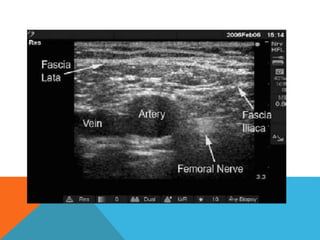

• Identify HYPERECHOIC oval or triangular shaped femoral nerve lateral

to the artery on the iliopsoas muscle, under fascia iliaca

• Femoral nerve triangle created by the femoral artery medially, fascial planes

anteriorly and the iliopsoas muscle posteriorly

Identification of the femoral nerve often is made easier by slightly tilting the

transducer cranially or caudally. This adjustment helps "brighten" up

the nerve and makes it appear distinct from the background

The goal is to place the needle tip immediately adjacent to the lateral

aspect of the femoral nerve, either below the fascia iliaca or between

the two layers of the fascia iliaca, into the wedge-shaped tissue space

lateral to the femoral artery.

Proper deposition of local anaesthetic is confirmed by observation of the

femoral nerve being lifted off of the surface of the iliopsoas muscle or

of the spread of the local anaesthetic above in the wedged-shaped

space lateral to the artery.